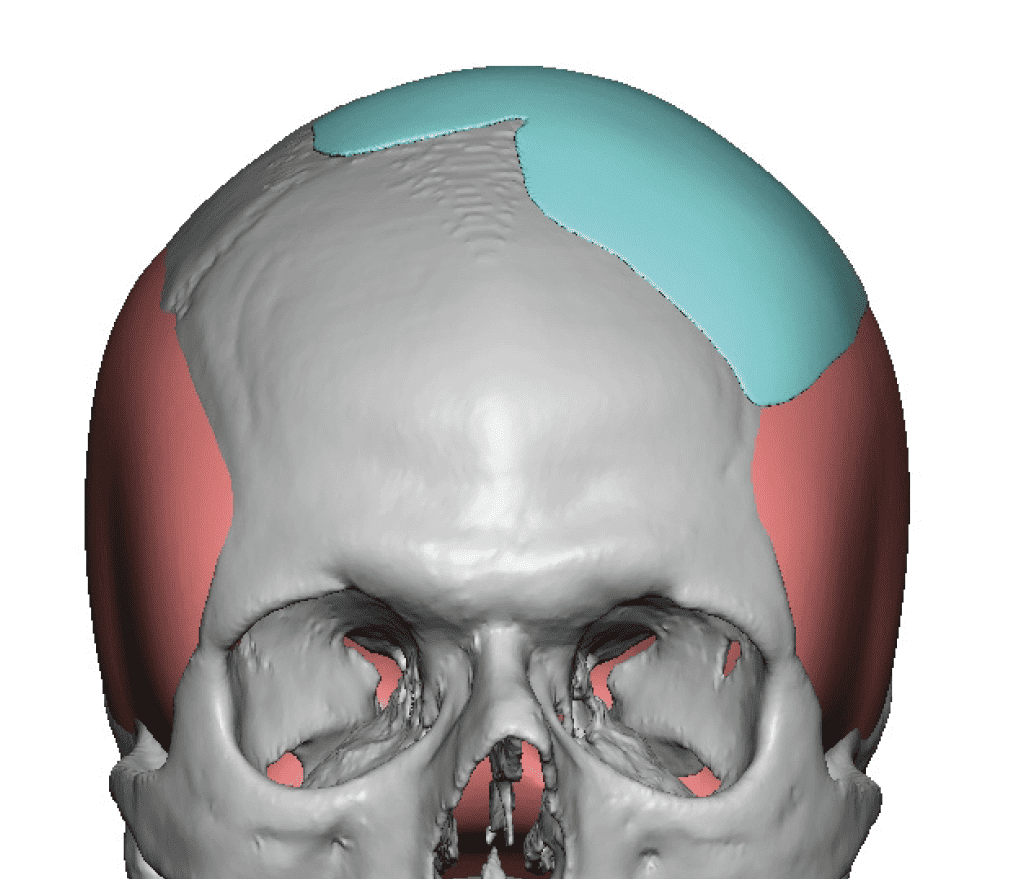

Patient 84

Desire for change of head shape from front view form an inverted V shape to a rounder and wider head shape.

Placement of custom extended forehead-temporal implants through incisions in the crease behind the ear. (he had a prior back of head skull implant which is green in the implant designs and which the head widening implants partially covered it)

Desire for change of head shape from front view form an inverted V shape to a rounder and wider head shape.

Placement of custom extended forehead-temporal implants through incisions in the crease behind the ear. (he had a prior back of head skull implant which is green in the implant designs and which the head widening implants partially covered it)